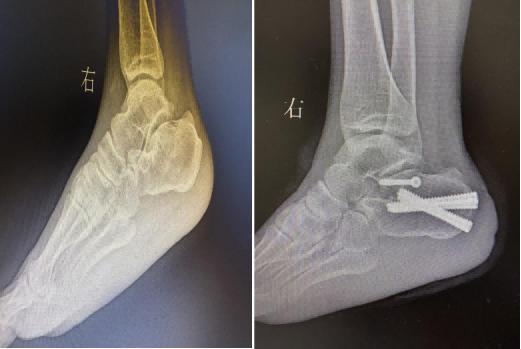

对于承重部位的骨折,创伤骨科团队同样以微创技术实现“高效修复”。62岁的王女士因高处坠落导致跟骨骨折,跟骨作为足部主要承重骨,骨折后易出现足弓塌陷。团队采用闭合复位空心钉内固定术,通过手法复位恢复跟骨解剖形态后,植入空心钉完成固定,避免了传统切开手术可能导致的皮肤坏死风险。